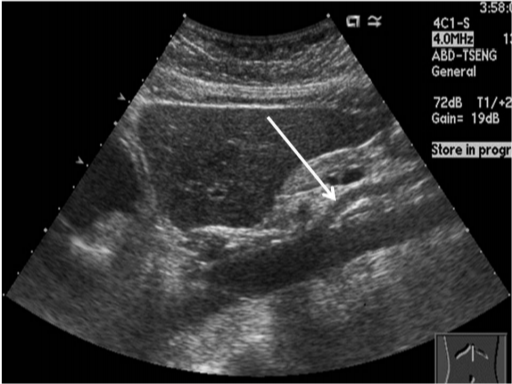

- 담낭결석(담석증): 담낭 내 결석 존재 여부, 크기, 위치 확인

- 담낭염: 담낭 벽의 두께 증가, 액체 저류 관찰 가능